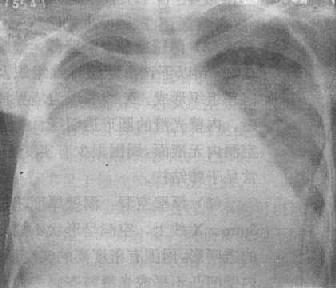

中量积液:液体量较多时,由于液体的重力作用而积聚于胸腔下部的肺四周,表现为下肺野均匀致密,肋膈角完全消失。膈影不清(图3-1-14)。由液体形成的致密影的上缘呈外高内低的斜形弧线。此弧线的形成是由于胸腔内的负压状态、液体的重力、肺组织的弹性、液体的表面张力等作用所致。实际上液体的上缘是等高,但液体的厚度是上薄下厚,液体包绕肺的周围,当摄影时,胸腔外侧处于切线位,该部液体厚度最大,因而形成外侧和下部密度高,内侧和上部密度低。

右侧胸腔中量积液

图3-1-14 右侧胸腔中量积液

右下肺野均匀致密,肋膈角与膈影不能分辨,

上缘模糊不清,心脏左移